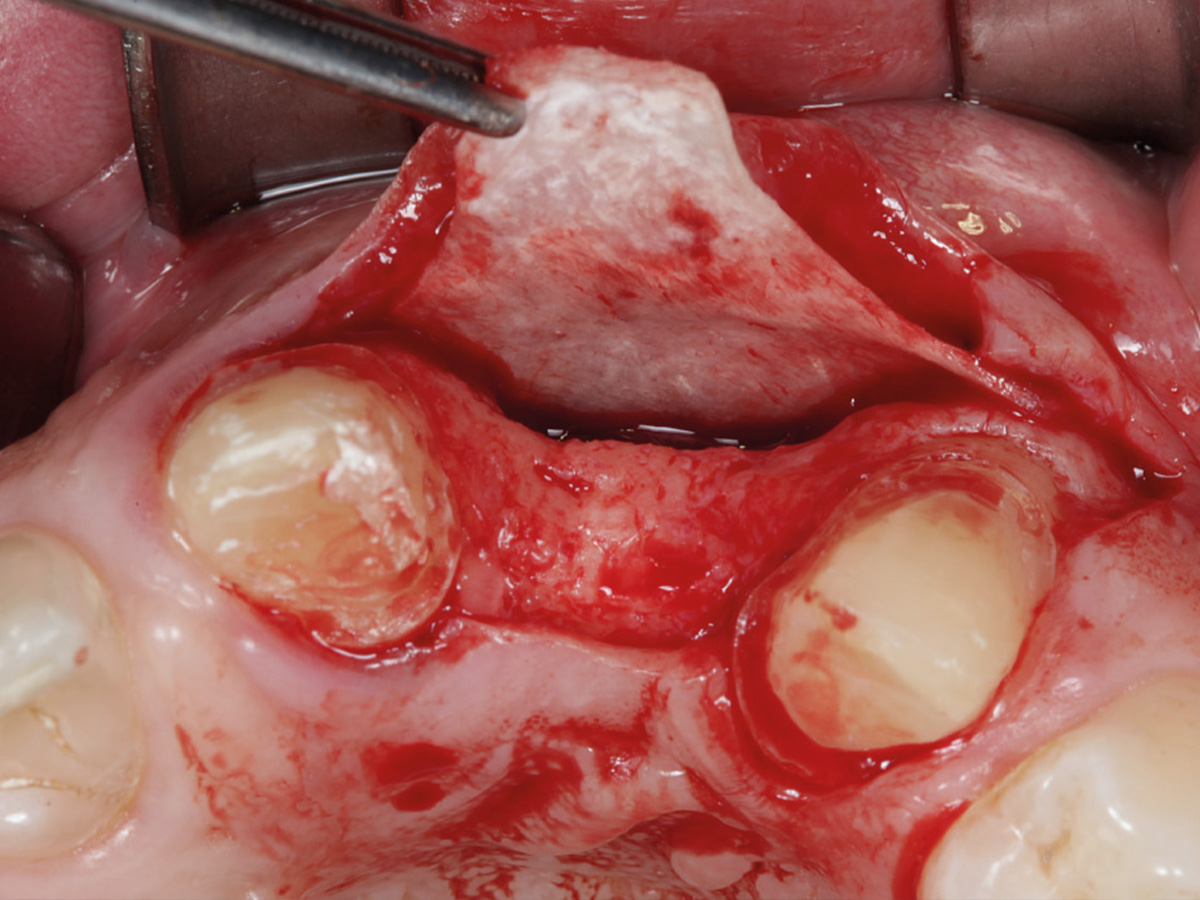

Abbildung 3

Nach Bildung eines Mukoperiostlappens wird mit der Bone Lamina die bukkale Lamelle rekonstruiert. Die Lamina wird mit Titanpins befestigt.